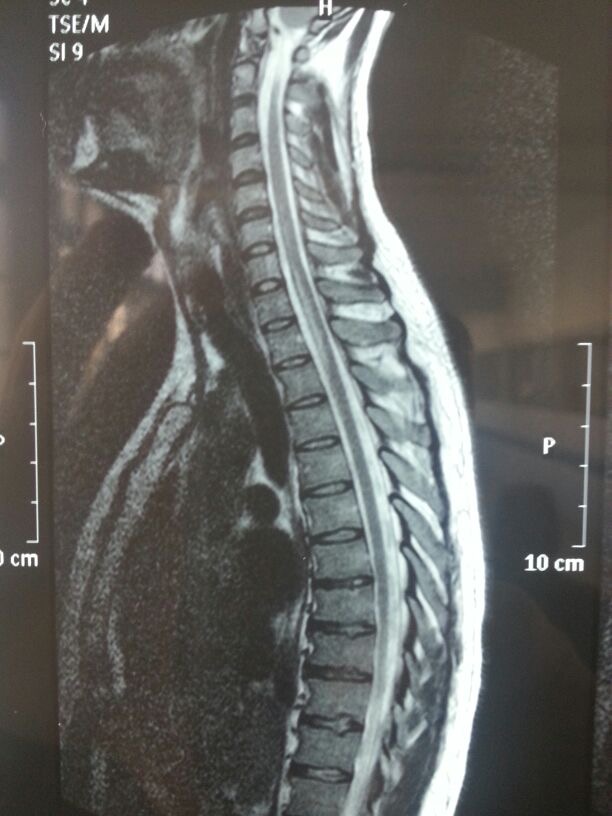

I met my wife in London in 2011. In 2012, she had to return to Chile, and I chose to follow her. In 2014, while I was studying for a PhD - which later converted to a second master's degree - I suffered a neurological disorder known as Transverse Myelitis, just 6 weeks away from our wedding day.

Transverse Myelitis is a disorder characterised by an inflammation of the spinal cord which led to me being paralysed from neck to toe. I was told by the neurologist that I could possibly never walk again which led me to question my life ambitions, career and family goals. For the sake of my dreams and future aspirations, I knew that I couldn’t give up and needed to do everything possible to resume a ‘normal’ adult life as a student and newly wedded husband. I went into rehab and slowly learned to walk again. I graduated with my second master’s degree in science 2 years and 3 months after the incident. I have learned to appreciate every aspect of life – my family, friends, being able to move – everything. To this day, I am 98.5% recovered.